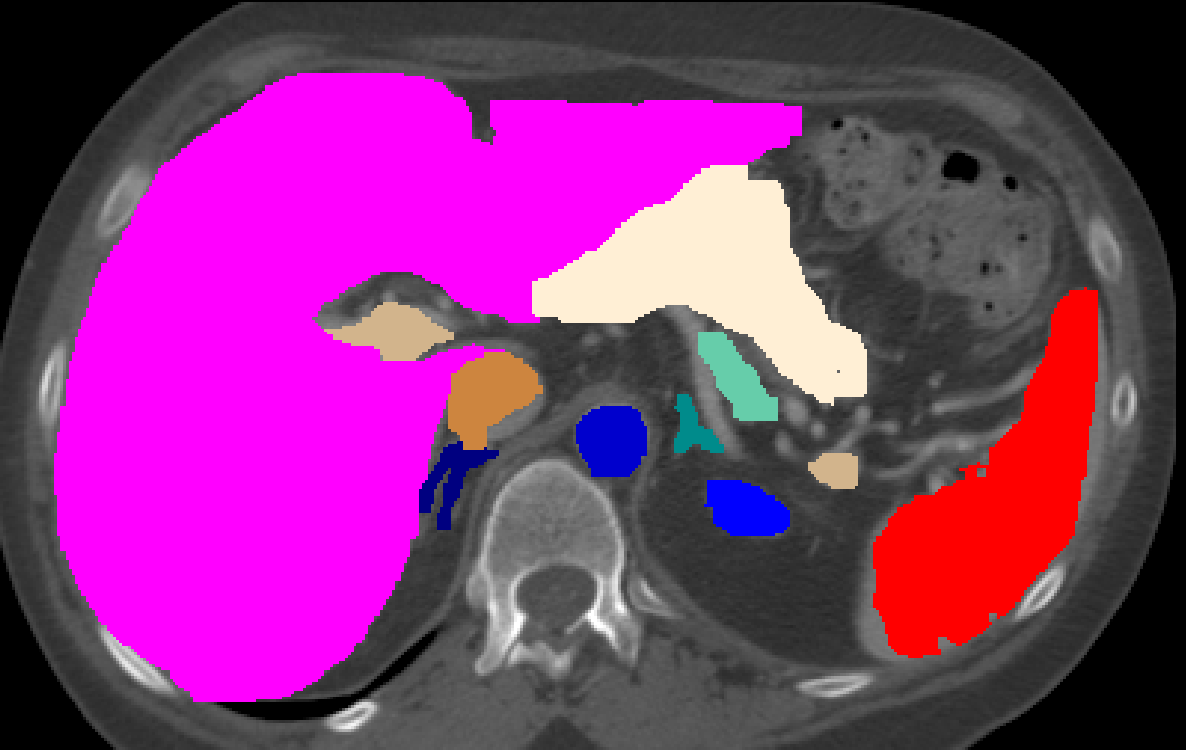

Manual Labels for Verification. We design a mechanism to validate these collected labels by humans. To do so we collect manual labels from 3000 2D image from 300 MRI samples for 10 abdominal organs (UKBOB-manual). These manual labels (see examples in Figure 2) act as a validation for the large UKBOB dataset. On these labels, the UKBOB automatic labels obtain an average Dice Score of 0.891 (see Table 3). Furthermore, we verify the spine labels of UKBOB using previously collected manual labels of 200 3D spine labels [5]. We show an example in Figure 1 and we see how the new collected labels match the manual labels in the spine with a total Dice score of 0.811, indicating accurate labels. We discuss in Section 5.1 another mechanism for verifying the labels by zero-shot generalization of trained models to other similar datasets that has manual labels.

Specialized Organ Label Filter (SOLF). While automatic labeling enables creating large datasets, it introduces the possibility of noisy or erroneous labels. To mitigate this, we propose a filtration mechanism that removes outliers from segmentation. A question arises on how to distinguish segmentation failures from common patient abnormalities, e.g. enlarged liver. It’s important to note that human organs follow typical geometric properties that arise from the body’s need to optimize function while minimizing energy expenditure and structural stress. They reflect the underlying biological "blueprint" that has been honed by evolution [64]. inspired by the evolutionary regularity of human organs [64], we propose the Specialized Organ Label Filter (SOLF), using three features jointly: normalized volume, eccentricity, and sphericity (illustrated in Figure 3).

For each organ class , the normalized volume for some 3D sample is computed as where is the voxel count for the organ and is the total body voxel count. We define acceptable bounds for each feature by excluding the extreme percentiles. For example, the bounds for volume are set as

| (1) |

, where denotes the -th percentile function. Sphericity is defined as , with computed from voxel counts and as the surface area measured by counting the exposed voxel faces of the organ. Finally, eccentricity is defined as , where and are the smallest and largest eigenvalues of the covariance matrix of organ voxel coordinates. A sample is flagged as inaccurate if at least two of the three features (normalized volume, eccentricity, and sphericity) fall outside their respective acceptable ranges. Setting for SOLF effectively discards samples with anomalous organ characteristics while retaining valid labels. A single patient with abnormal organs is extremely unlikely to have more than a single independent aspect of deviation at the same time, hence indicating inaccurate labels.

We filter collected organ labels using the patient’s full-body statistics, a novel approach compared to previous methods that rely on flat label statistics (IQR) [10, 38] rather than patient meta-information and organ-specific features .